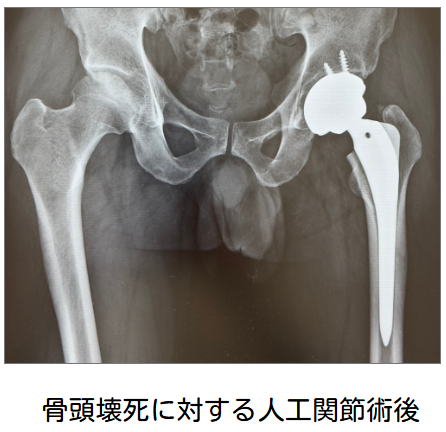

変形性膝関節症に対する手術治療

保存療法で十分な効果が得られず、日常生活に支障がある場合は、手術を検討します。手術には、自分の関節を残す「骨切り術」や、人工の関節に置き換える「人工膝関節置換術」などがあります。人工膝関節置換術(TKA)は、変形性膝関節症が進行して、痛みや歩きにくさが強くなった膝に対して行う手術です。すり減って傷んだ関節の表面を整え、金属と特殊な樹脂(ポリエチレン)でできた人工関節に置き換えることで、痛みを軽くし、日常生活動作を改善することを目的とします。TKAは末期の変形性膝関節症に対して、世界的に広く行われている標準的な治療の一つです。頻度は高くありませんが、手術である以上、感染、血栓(足の血のかたまり)、出血、腫れ、可動域制限、しびれ、痛みの残存、人工関節のゆるみ・摩耗などのリスクがあります。

当院では手術は行っておりませんが、連携している専門の医療機関をご紹介します。手術が必要な場合でも、術後のリハビリテーションは当院で継続して行うことができます。